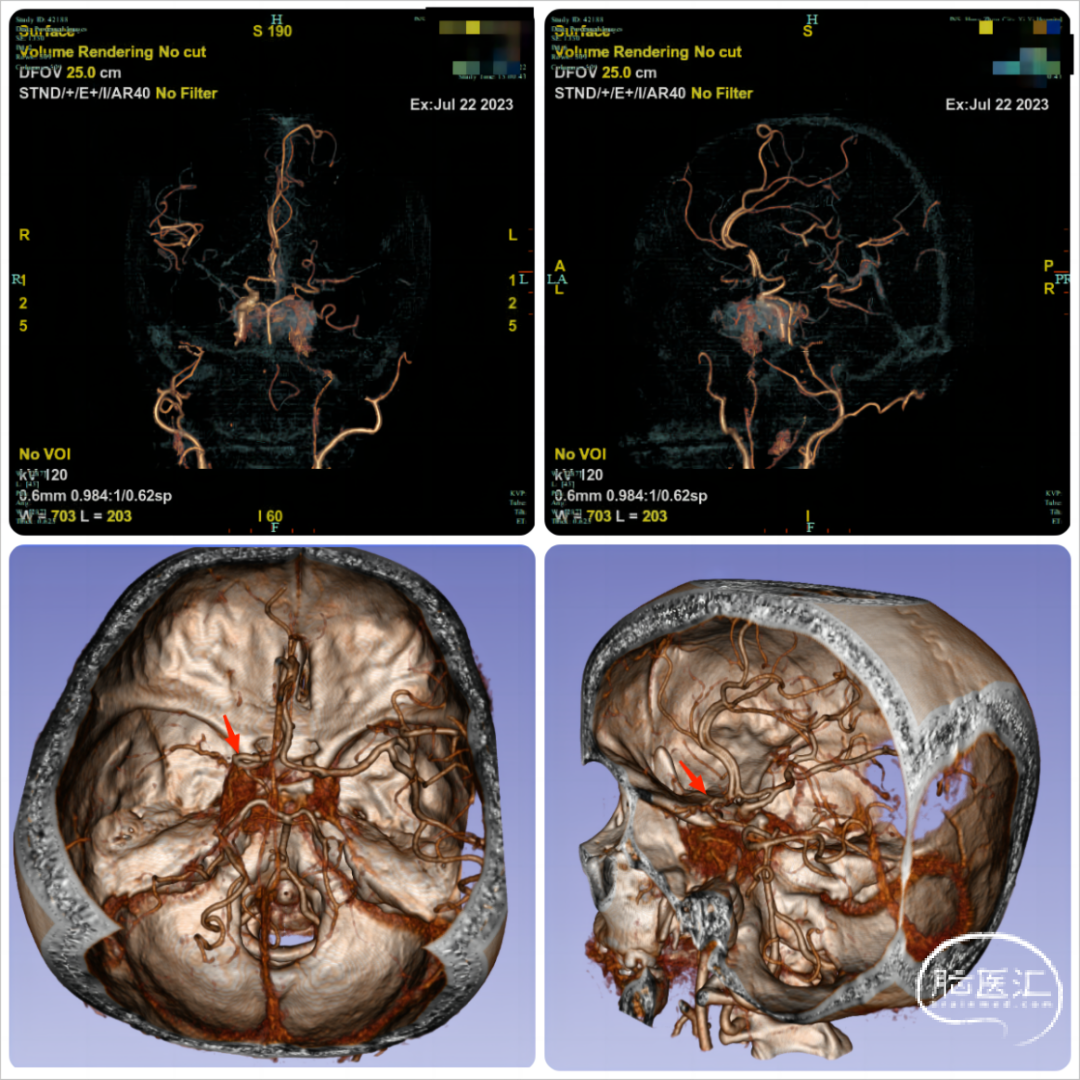

脑血管造影检查:术中见右侧颈内动脉眼动脉段以远变细,左侧大脑中动脉M1段消失,烟雾样血管增生(图3、4)。后循环无明显向前代偿。

图3. ①③右侧颈总动脉造影;②④左侧颈总动脉造影

图4. 脑血管造影3D合成图像